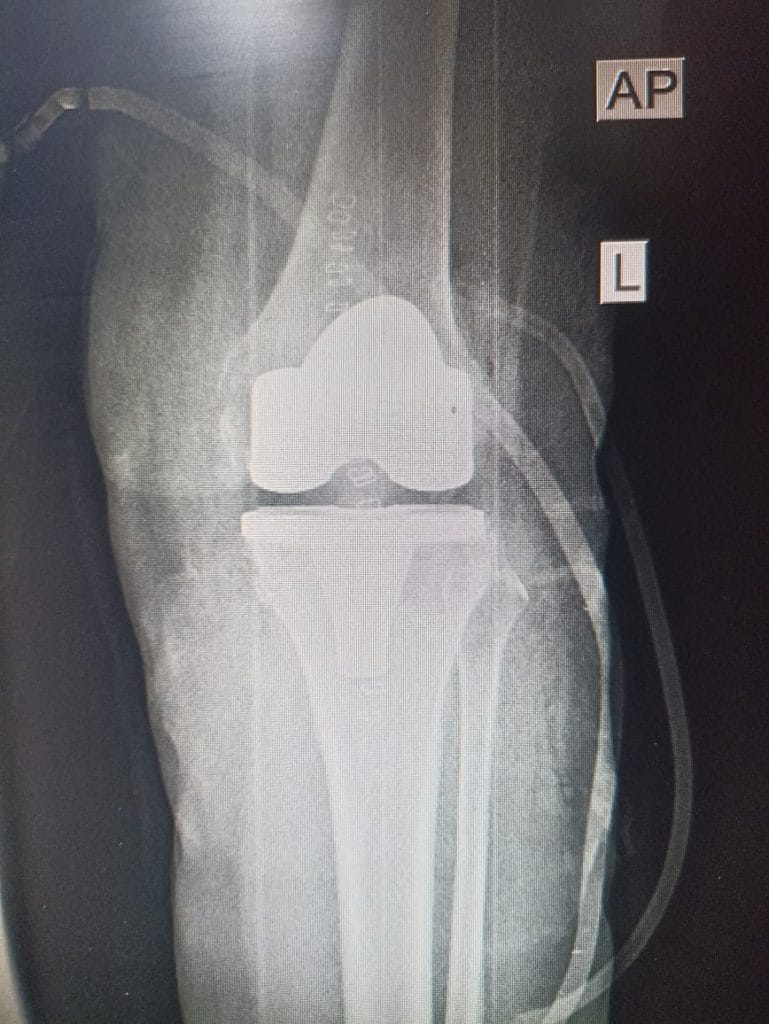

اجرى فريق طبي جراحي في مركز ابن سينا التخصصي لجراحة العظام والكسور و تبديل المفاصل عملية تبديل مفصل الركبه اليسرى لمريضة تبلغ من العمر 59 سنة

اجريت لها العملية الجراحية والمريضة الان بحالة جيدة و الحمد لله.

وتألف الفريق الطبي الجراحي كلاً من د. حسن هادي و د. يوسف علاء و د. فراس فؤاد اختصاص جراحة العظام و الكسور و د قاسم عبدالله اخصائي التخدير .